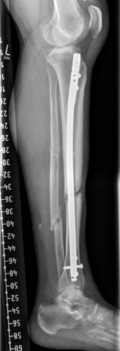

Von der Fraktur über die Pseudarthrose zum Segmenttransport

Vorgeschichte: Herr M. zog sich vor drei Jahren im Rahmen eines BG-lich versicherten Motorradunfalls eine I°ig offene mehrfragmentäre Tibiaquerfraktur mit 2-Etagen-Fraktur der Fibula links sowie eine OSG-Luxationsfraktur rechts zu.

Die initiale Versorgung erfolgte in einer Klinik der Maximalversorgung mit Fixateur extern Anlage und Transfixation des Sprunggelenks. Im Verlauf erfolgte der Verfahrenswechsel auf einen Tibia-Nagel links und Fibulaplatte mit Zuggurtung des Innenknöchels rechts.

Bei Fistel über der Unterschenkelfraktur links erfolgte etwa 9 Monate nach dem Unfall die Fistelexzision, mehrfaches Markraummüberbohren mit Jet-Lavage sowie die erneute Wundunterdruck-Therapie. Bei Keimnegativität erfolgte eine erneute Marknagelosteosynthese mit Schwenklappenplastik und Spalthaut zum Verschluss des Defekts.

Rekonstruktion: Bei Infektverlauf mit Nachweis von Staphylococcus aureus und Staphylococcus epidermidis sowie histologischem Nachweis einer chronischen Osteomyelitis an der linken Tibia erfolgte 1,5 Jahre nach dem Unfall die Infektsanierung mit Segmentresektion und anschließend der Segmenttransport mittels Precice-Bone-Transport-Nail.

Nach etwa 2 Monaten konnte das Kompressionsdocking erfolgen. Bei weitgehender Konsolidierung über ein Jahr nach der Implantation erfolgte die Metallentfernung des einliegenden Segmenttransport-Nagels sowie die Anpassung eines Braces zur weiteren Ausbehandlung.

Resümee: Erst durch die konsequente Segementresektion konnte der Infekt eradiziert werden. Durch die Therapie mit dem noch relativ neuen Verfahren des Segmenttransportnagels konnte dem Patienten die zwar ebenfalls meist erfolgreiche, jedoch deutlich belastendere Therapie mit einem Ringfixateur erspart werden.